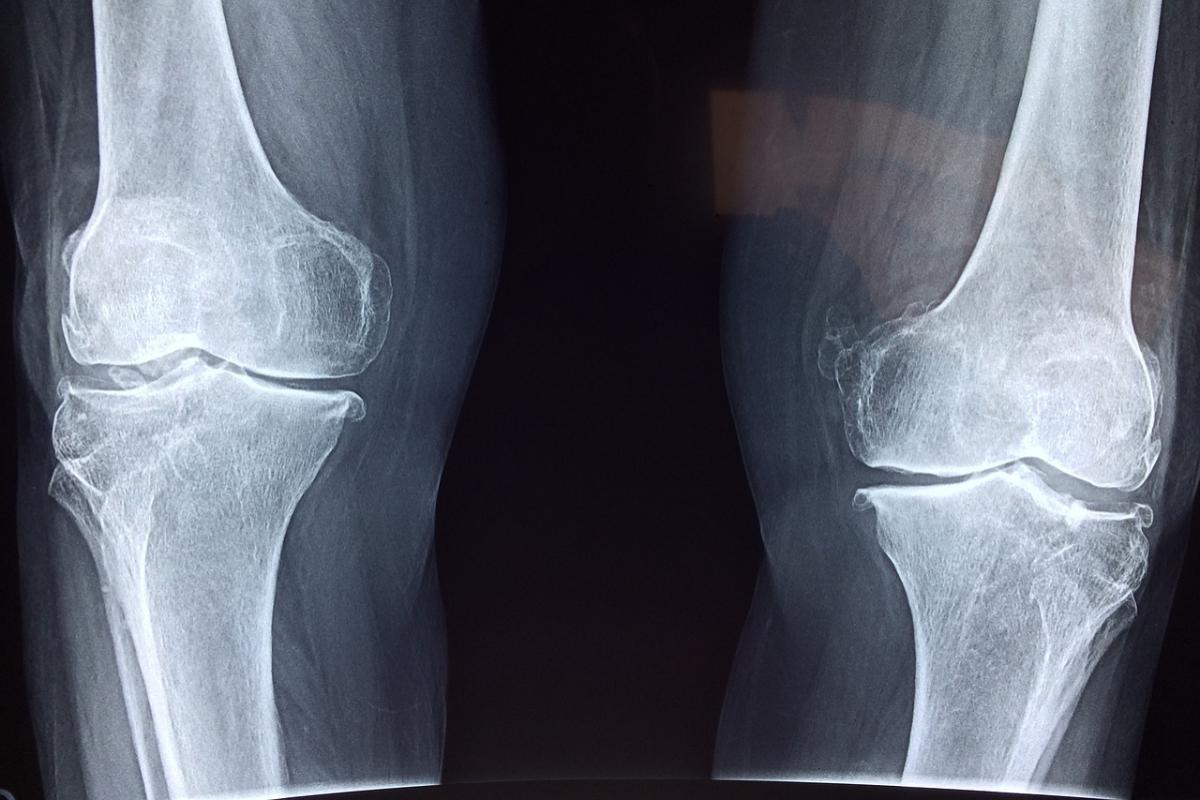

Фото: Dr. Manuel González Reyes / Pixabay.com

Он уточнил, что очередь по замене тазобедренного сустава составляет 11 779 человек, по коленным суставам – 14 058. Число необходимых замен тазобедренного сустава с 23 мая 2023 года сократилось на 17%, коленных – на 10% с той же даты.